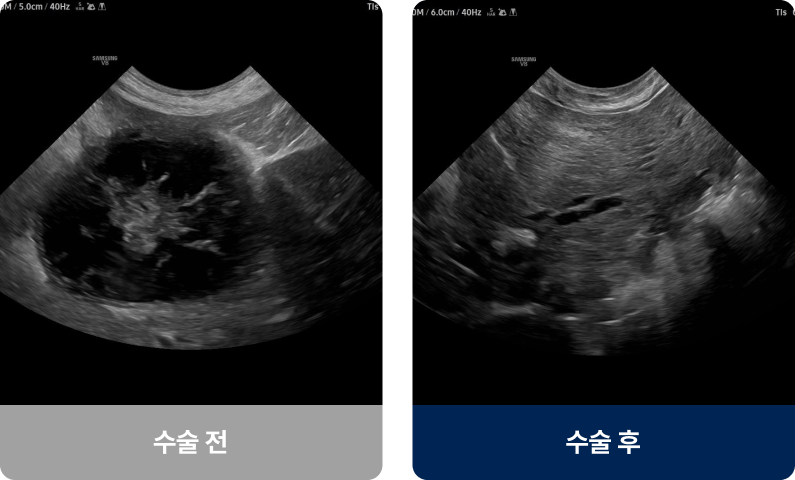

간·비장·폐·피부·유선 등 다양한 장기에 비정상 세포 덩어리(종양)가 생긴 상태로, 양성과 악성으로 나뉘며 유전적 요인, 호르몬, 비만 등이 영향을 줄 수 있습니다. 노령견에게 발병률이 높으며, 몸에 만져지는 혹·식욕 저하·기력 저하·복부 팽만·기침 증상을 보입니다.

외과적 치료법(수술적 치료)

| 종양 절제술 | 광범위 절제술 | 기관 절제·재건술 | |

|---|---|---|---|

| 수술개요 | 종양 부위만 선택적으로 절제 |

종양 주변 정상 조직까지 절제 |

장기에 생긴 종양 절제 후 기능 재건 |